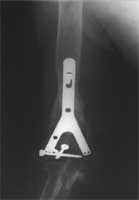

肱骨远段骨折,骨缺损。多次手术失败      准备植入的大块异体骨13厘米长,采用Y型钢板固定

恢复上肢长度,大块异体骨植骨修复骨缺损、Y型钢板固定     术后X线片,显示骨缺损已经愈合